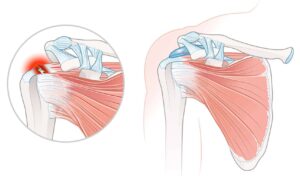

Die Orthopädie ist ein medizinisches Fachgebiet, das sich mit der Prävention, Diagnose und Behandlung von Erkrankungen und Verletzungen des Bewegungsapparates beschäftigt. Knochen, Gelenke, Muskeln, Sehnen und Bänder müssen gemeinsam funktionieren, um uns Beweglichkeit und Stabilität zu ermöglichen.

Auf unserer Seite finden Sie umfangreiche Informationen zu orthopädischen Beschwerden und Erkrankungen. Von der Arthrose über Bandscheibenvorfälle bis hin zu Kreuzbandriss und weiteren Sportverletzungen: wir geben Ihnen einen Überblick über die häufigsten orthopädischen Krankheitsbilder, wie sie behandelt werden können und inwieweit ein Bildgebungsverfahren, wie eine (z.B. MRT Knie, Rücken MRT) bei der Diagnose bei der Diagnose unterstützend wirken können.